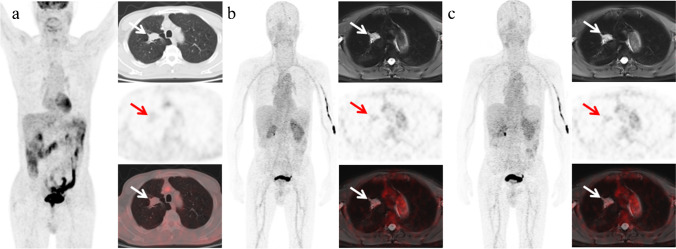

A 63-year-old patient with primary tumor of lung cancer (poorly differentiated adenocarcinoma) had accepted multiple chemotherapy and was enrolled to evaluate the therapeutic effects. He underwent a routine 18F-FDG PET/CT and two 68Ga-cyc-DX600 PET/MR at 50 min P.I. and 80 min P.I. successively (Fig. 5). After multiple chemotherapy, only slight FDG uptake (SUVmax = 2.36) were visually observed in lesion in 18F-FDG PET/CT indicating an effective inhibition of tumor activity, while lesion was of high 68Ga-cyc-DX600 uptake at 50 min P.I. (SUVmax = 2.36) and 80 min P.I. (SUVmax = 3.43). Notably, compared with images at 50 min P.I., there was a comparable but a slight higher ratio of target to background at 80 min P.I. (TBR50 = 4.23; TBR80 = 4.73); hence, 68Ga-cyc-DX600 PET provided a long observation window and was operable in a dual-phase scan protocol, and images were both of a relatively clear background, while a relatively favorable ratio of target to background at 80 min P.I. for this patient.

Fig. 5.

FDG PET and dual-phase ACE2 PET of a 63-year-old man who had accepted multiple chemotherapy for lung cancer (poorly differentiated adenocarcinoma). Slight FDG uptake in lesion was detected on 18F-FDG PET/CT (a); lesion was of high tracer uptake in images both at 50 (b) and 80 (c) min P.I., comparatively, of a better TBR at 50 min P.I